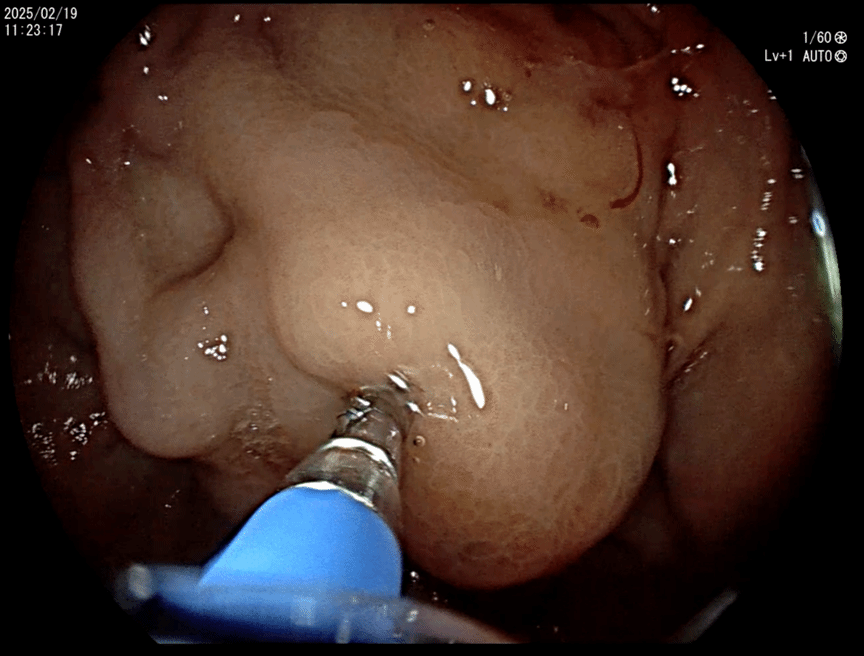

2月19日,我院消化内科超声内镜团队成功开展我院首例超声内镜(EUS)引导下弹簧圈联合组织胶精准栓塞术,为肝硬化合并胃底静脉曲张破裂出血患者提供创新性治疗解决方案。该手术标志着我院在门脉高压并发症及EUS介入治疗领域实现技术突破。

本次手术由消化内科史海涛副主任、马师洋副教授、赵菊辉副教授及袁佳医师组成核心术者团队,依托超声内镜系统,创新性采用"弹簧圈骨架支撑+组织胶生物封堵"双联疗法。术中使用多普勒超声实时导航技术,精确定位大小为3×2.5cm的曲张静脉团块。通过预载式FNA穿刺系统,将医用级钛合金弹簧圈精准植入曲张血管腔道形成物理支撑,继而注入医用组织胶与聚桂醇复合制剂,在血管腔内形成稳定的生物-机械复合栓塞体。与传统内镜治疗方法相比,该术式具有显著优势。一方面,能够借助超声多普勒实时评估血流动力学变化,实时监测手术进程,最大程度规避误穿风险;另一方面,持久的栓塞效果有效降低了再出血率,同时巧妙地规避了异位栓塞风险,极大减少了术中出血风险,为患者的生命安全提供了更有力的保障。